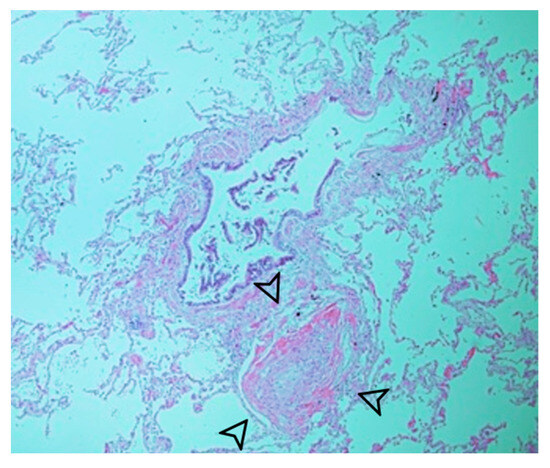

The patient underwent a lobectomy along with feeding artery ligation using an endocutter device (Echelon Flex Power Plus Cutter 60 mm, Ethicon, Cincinnati, OH, USA). Pathological examination revealed the presence of a systemic feeding vessel without notable thickening or atherosclerotic changes (Figure 3). The alveoli exhibited well-developed structures with nonspecific enlargement (Figure 4), appearing clean without inflammatory alterations or mucostasis. Lymph node examination revealed lymphoid hyperplasia, with no pathological evidence of aortopulmonary fistula. The patient did not exhibit any complications upon discharge or at the 3-month follow-up.

Figure 3.

Systemic feeding vessel (arrowhead) with no significant thickening or atherosclerotic alterations.